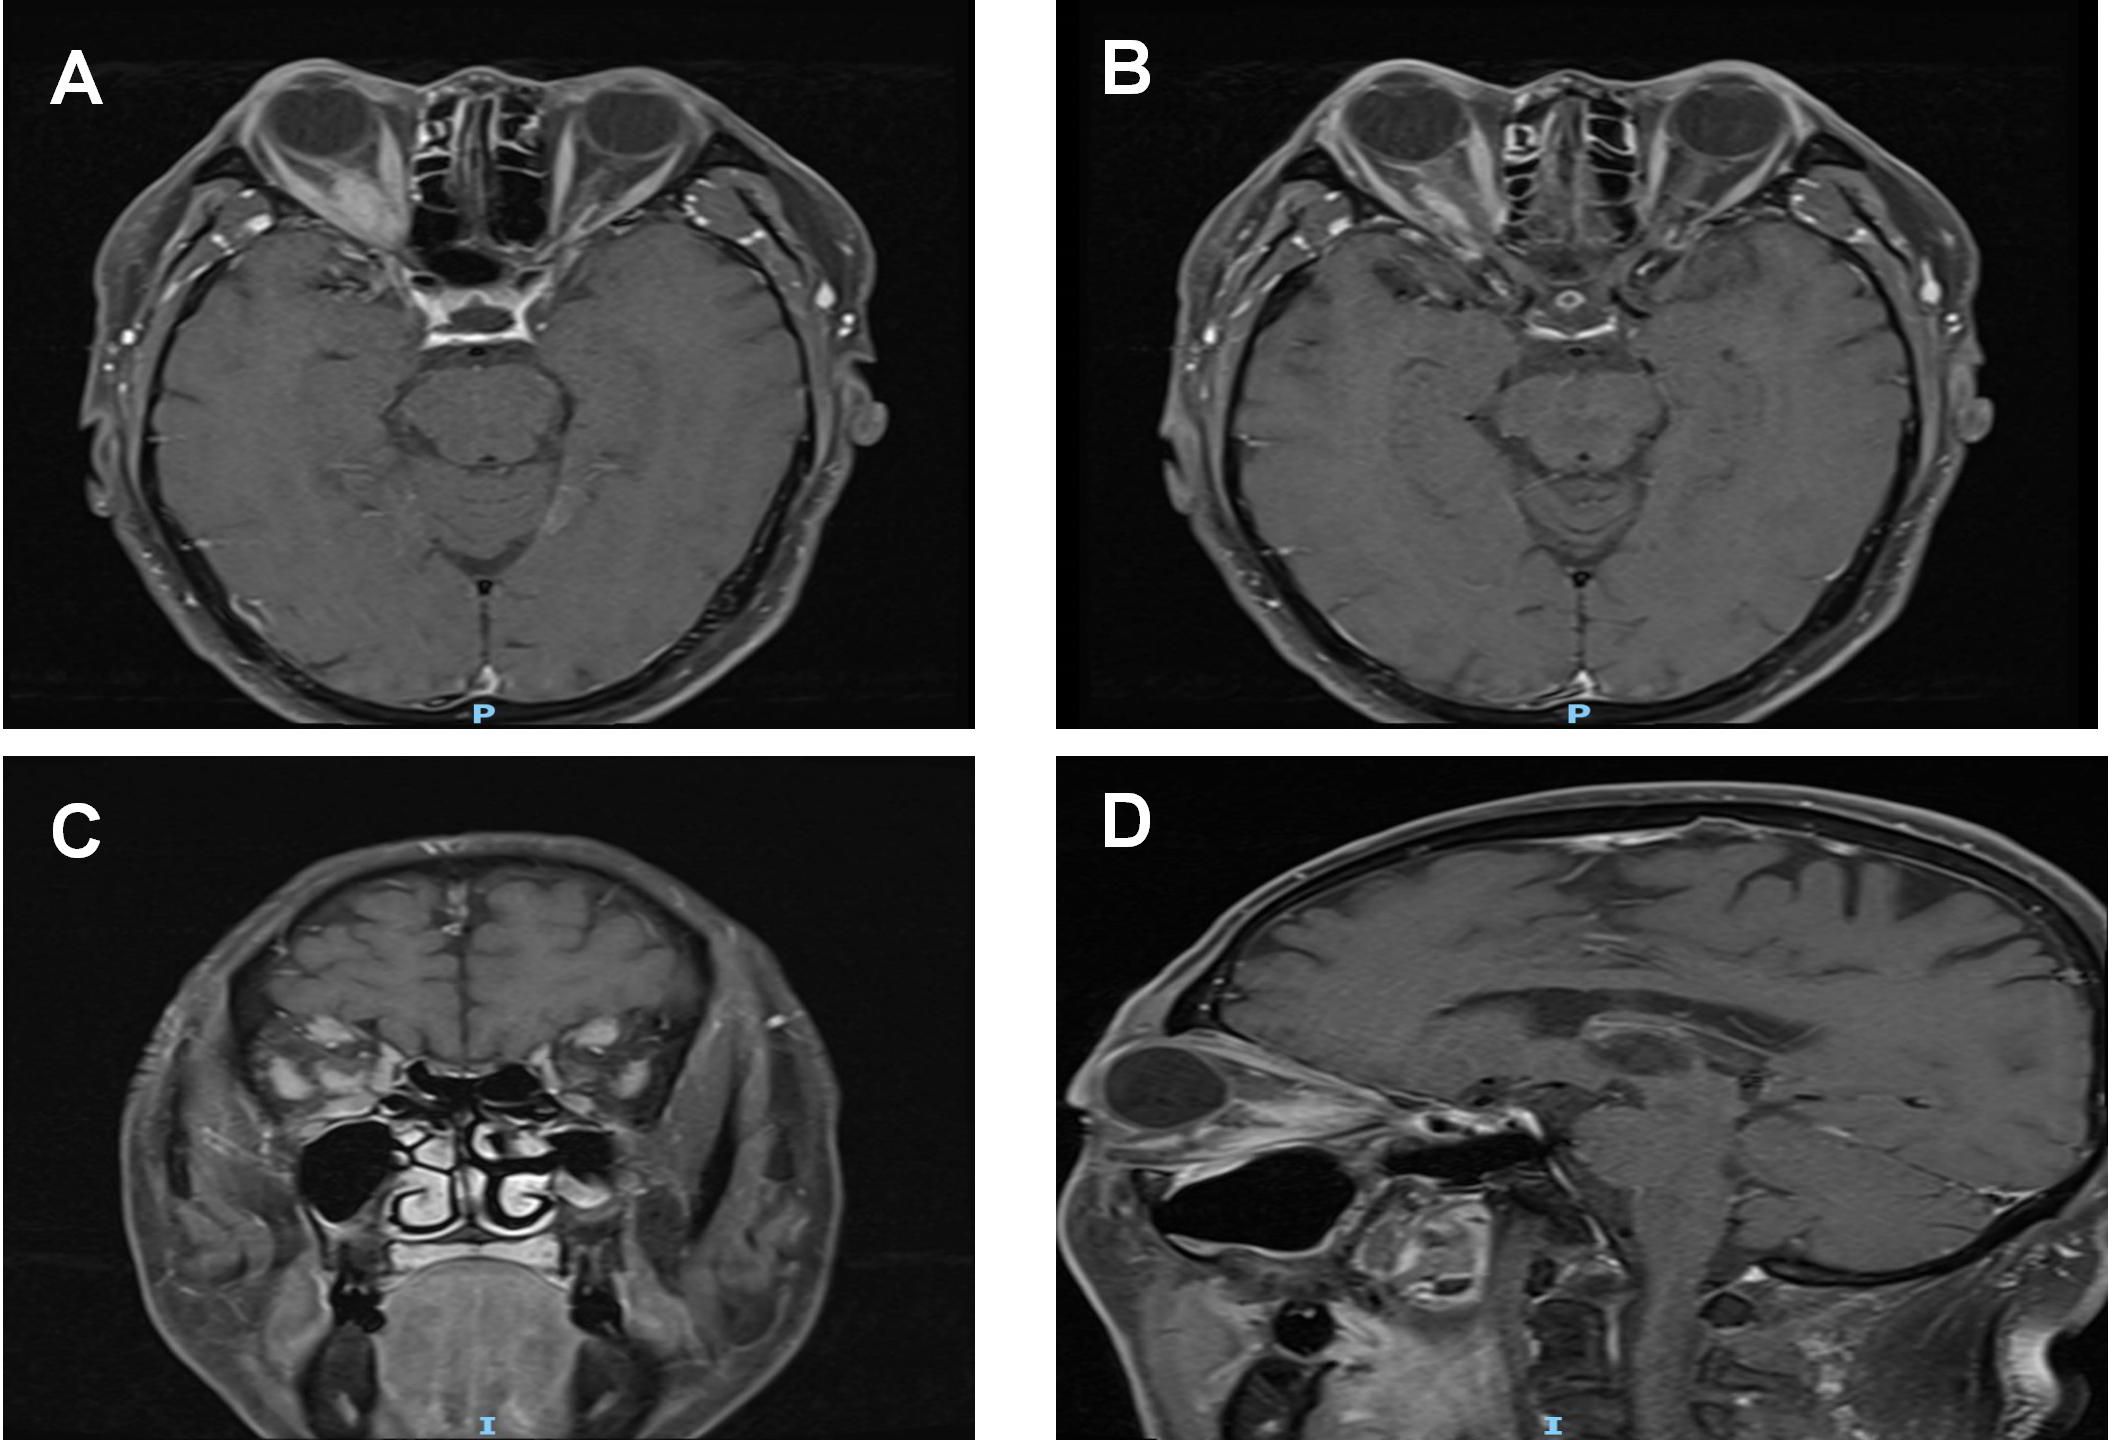

Figure 3

Post-treatment MRI orbital plain scan + contrast enhancement: (A, B) The mass around the right optic nerve has shrunk to 16 mm × 9 mm (a 20% reduction compared to pre-treatment), with clearer borders than before and a distinct boundary from the optic nerve. The thickness of the right medial rectus and lateral rectus muscles has decreased to 4 mm (approaching the normal range), the volume of the lacrimal gland has shrunk to 14 mm, and the degree of enhancement has weakened after contrast administration. (C, D) T1WI coronal and sagittal images, respectively.